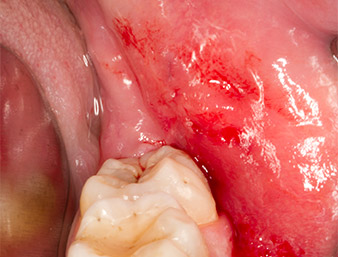

After block and local anaesthesia, the operating site was opened up and the soft tissue exposed for buccal retromolar access (Fig. 3).

The tissue above the root remnant was not completely ossified and consisted for the most part of granulation tissue modified by inflammation (Fig.4).